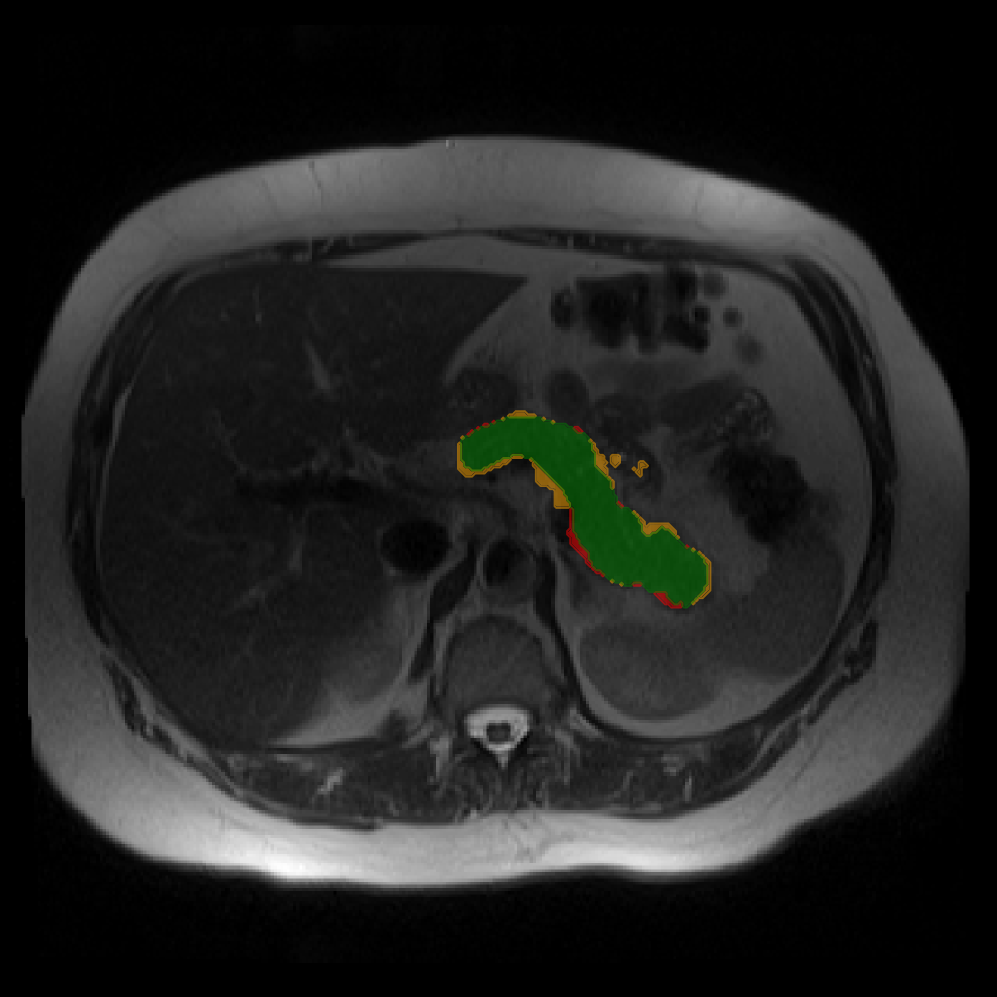

Accurate pancreas segmentation is a critical prerequisite for precise cyst analysis and classification. Recently, we developed PanSegNet [zhang2025large], a novel segmentation architecture incorporating linear self-attention layers [zhang2022dynamic] within the nnUNet framework [isensee2021nnu] to enhance global information modeling capabilities while maintaining computational efficiency (Fig. 1). PanSegNet demonstrated exceptional segmentation performance across both T1W and T2W modalities, achieving mean dice scores of 86.817.30% and 89.626.38%, respectively (Table 1, Fig. 2b-c). This performance significantly exceeded that of Swin-UNETR [hatamizadeh2021swin], one of the most used state-of-the-art transformer-based medical segmentation models, which achieved dice scores of 79.091.40% and 76.290.66% for T1W and T2W, respectively (). In this study, we integrated PanSegNet into our Cyst-X engine along with a classifier for risk prediction. In Section 2.2, we show that the choice of segmentation model affects the classification results. The performance advantage of PanSegNet was consistent across all seven medical centers, demonstrating robust generalization despite variations in imaging protocols and equipment (Table 1). This cross-institutional reliability is particularly important for clinical applications, where model performance must remain consistent regardless of imaging site or acquisition parameters.

Each patient was categorized into one of these three ground truth classes: no risk/control, IPMN low-risk, or IPMN high-risk. To evaluate variability in image acquisition, we applied uniform manifold approximation and projection (UMAP) to image quality indicators, revealing distinct clustering patterns by imaging center and slice thickness. This heterogeneity reflects real-world clinical variability, enhancing the dataset’s generalizability while presenting technical challenges for model development. Fig. 6 shows examples of low-grade, high-grade, and cancer developing IPMNs from the Cyst-X dataset.